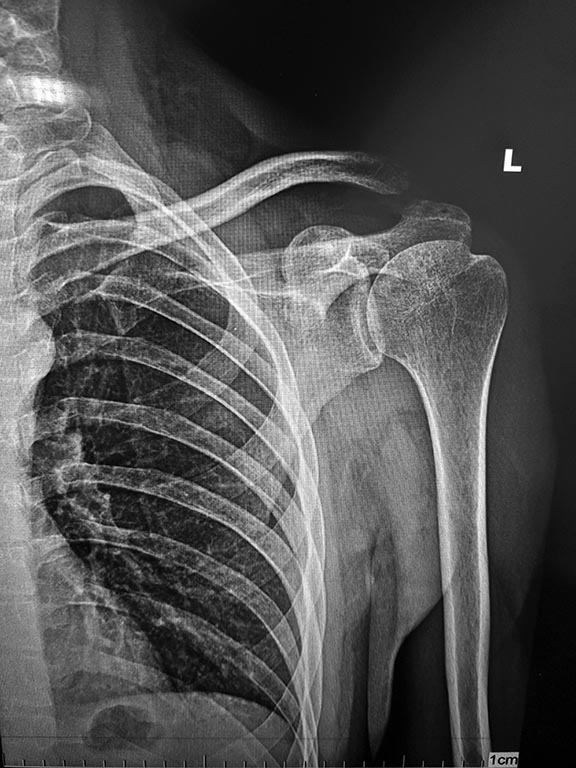

Застарелый вывих ключицы, разрыв АКС |

Застарелый вывих ключицы. Какой тип фиксации выбрать и нужна ли пластика? В середине апреля этого года получил травму плечевого сустава, вывих акромиального конца левой ключицы. Около месяца рука беспокоила, были боли. Потом боли прошли и остался дискомфорт в районе ключицы, она выпирала вверх, ограничений в движении не было. В июле была проведена операция, открытое вправление вывиха акромиального конца ключицы, произведена пластика связок капроновым шнуром с фиксацией двумя спицами и повязкой дезо на шесть недель. Недавно был на приёме у травматолога, подвывих сохраняется, наблюдается выпячивание ключицы и эффект клавиши при нажатии на неё, неприятные ощущения и щелчки при движении рукой. Врач рекомендует фиксацию крючковидной пластиной без пластики связок. Нужно ли делать пластику ключично-клювовидной связки? Какой тип фиксации лучше выбрать в моём случае? Снимок после первой операции прилагаю.